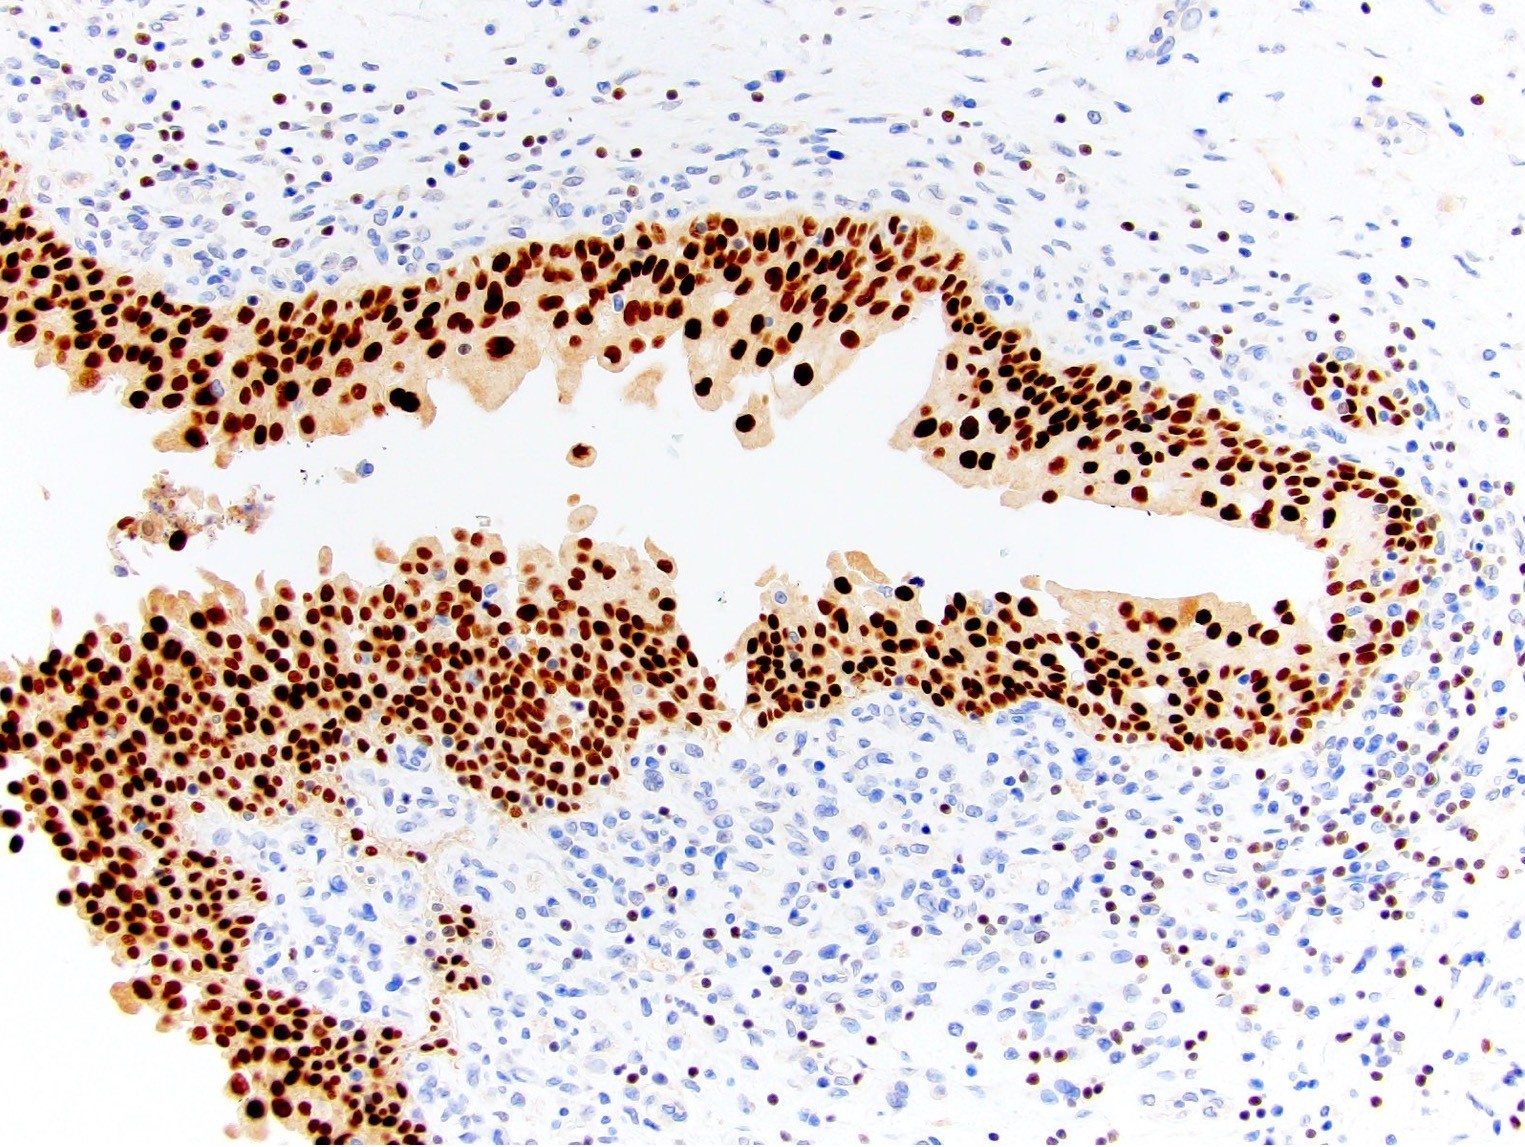

Microscopic (histologic) images

Contributed by Emily S. Reisenbichler, M.D., Andrey Bychkov, M.D., Ph.D., Maria Tretiakova, M.D., Ph.D. and Debra Zynger, M.D.

Positive staining - normal

Positive staining - tumors